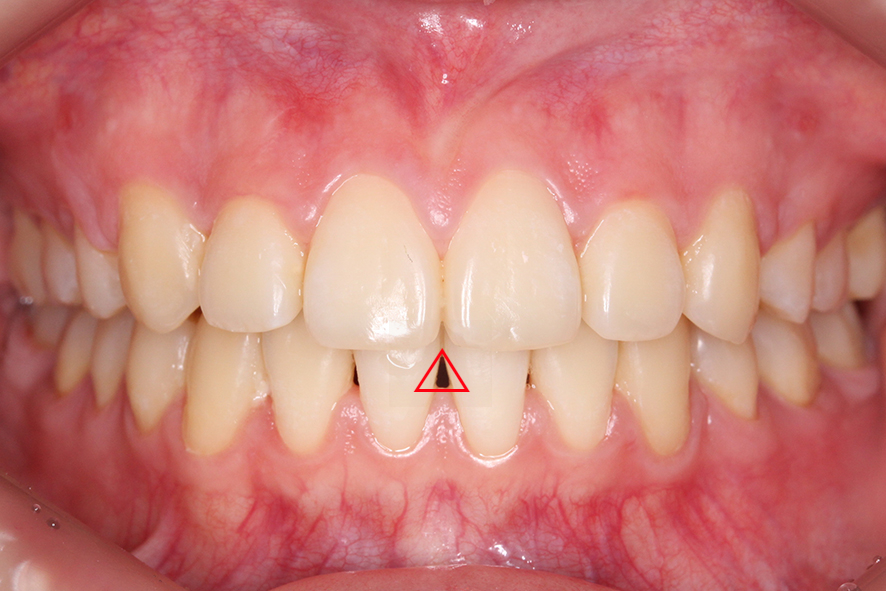

입돌출 Case의 데이몬교정 후 모습입니다.

교정 전 상악과 치석에 가려져

잘 보이지 않았던 블랙트라이앵글이

하악 중절치 사이에 보이는 모습인데요,

블랙트라이앵글의 경우 잇몸이

퇴축되면서 나타나는 증상으로

치아색과 흡사한 레진을 덧대거나

무삭제 라미네이트 세라필름을 부착하여

반영구적으로 빈 틈을 커버할 수 있습니다.